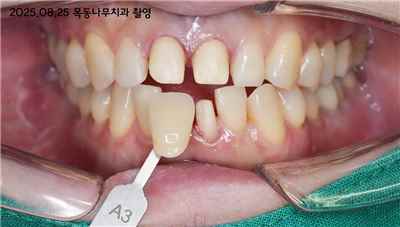

치아 변색 내부 원인

여드름 치료를 위해서 미노사이클린 복용으로 약간 파랗게 변색된 치아 (출처: Lee Ann Brady DMD)